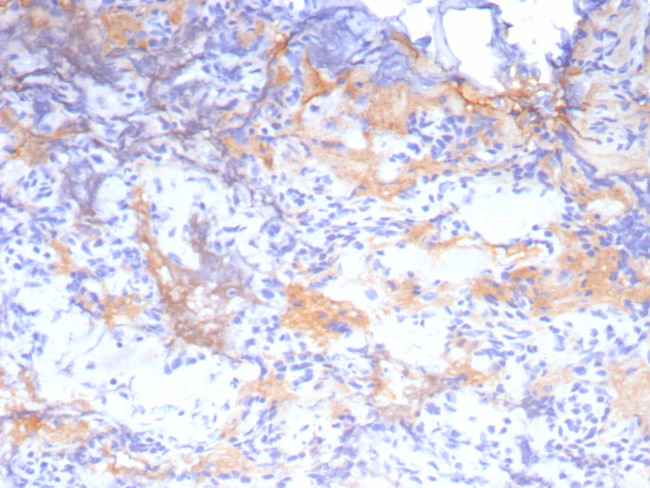

Growth Hormone (Pituitary Marker) Antibody in Immunohistochemistry (Paraffin) (IHC (P))

Growth Hormone (Pituitary Marker) Antibody (2688-RBM11-P1ABX) in IHC (P)

Formalin-fixed, paraffin-embedded human pituitary stained with Growth Hormone Recombinant Rabbit Monoclonal Antibody (GH/8215R). HIER: Tris/EDTA, pH9.0, 45 min. 2 °: HRP-polymer, 30 min. DAB, 5 min. {{ $ctrl.currentElement.advancedVerification.fullName }} 验证信息 View more